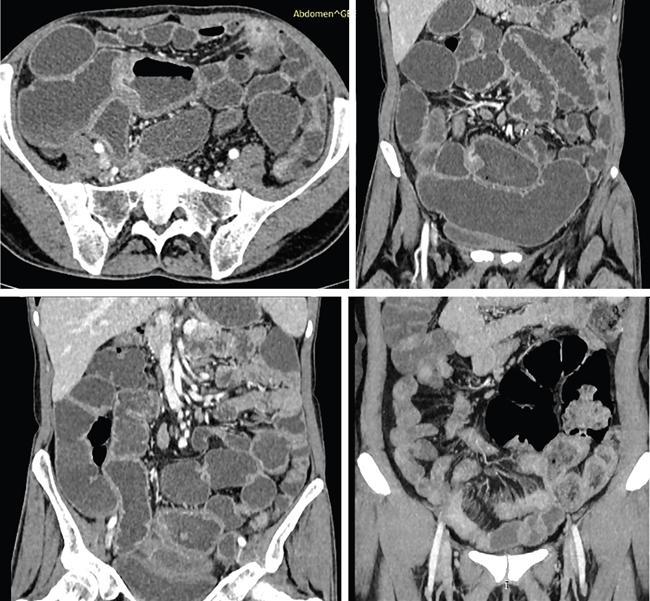

Computed tomography

CT enterography

CT enteroclysis